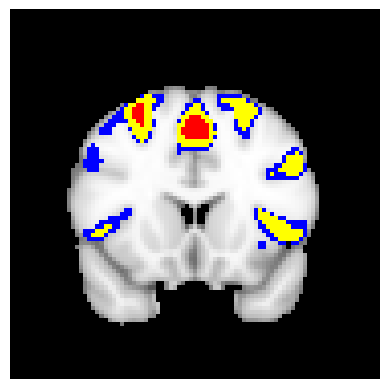

The confidence regions are constructed on fMRI scans from 77 subjects as a real data application of the proposed methods after applying additional smoothing with Gaussian kernel with FWHM to match the results shown in Bowring (2019) [BOWRING2019116187]. Confidence regions using 1) the joint method with , 2) the separate method with BH adjustment for upper and lower side each with , 3) the separate method with BH adjustment for upper side and two-stage adaptive procedure for lower with , and 4) SSS () were compared with threshold level 1.0%, 1.5%, and 2.0% Blood Oxygenation Level Dependent (BOLD) change. Joint control confidence regions are produced with instead of 0.05 for the reasons mentioned in chapter 3.

For all slices, FDR controlling methods show tighter inference of both upper and lower CR compared to the SSS method. SSS shows smaller upper CR and larger lower CR which suggests more conservative inference compared to FDR controlling testing based methodologies. This is due to the fact that by controlling for FDR, the method allows for more false discoveries in exchange for more discoveries in general. Despite having higher level at , joint control confidence regions still show comparable results to other methods even with higher significance level. Naturally, as the threshold goes up, the area enclosed between the upper and lower confidence regions decreases.

Confidence regions with separate controls of FDR for lower and upper are presented in two forms for comparison: one with BH procedure for the lower confidence region, and the other one with the two-stage adaptive procedure for the lower confidence region. The upper confidence region remains the same as both methods uses BH procedure for the upper set FDR control. Lower confidence regions with adaptive method are smaller than lower sets with BH procedure which is to be expected as the two-stage adaptive procedure is less conservative when more voxels are thought to be rejected. In the context of negative one-sided testing, this is equivalent to when there are less number of voxels above than below .